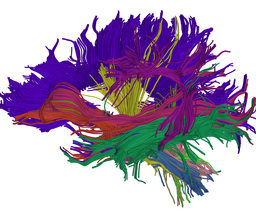

We are developing tools in the 3D Slicer for automatic clustering of tractographic paths through diffusion tensor MRI (DTI) data. By grouping tractographic paths based on shape and location, the white matter architecture may be more clearly visualized, and interesting properties of the clusters (such as for example FA or Westin's linear measure) may be quantified.

Our implementation uses spectral clustering, a method for grouping data using eigenvectors of a data affinity matrix. This image gives an overview of the method. On the left example input tractographic paths are shown (these were created by manually seeding in the 3D Slicer). The center image shows an embedding of the tracts as points in 2D, where the distance between points is related to their shape similarity. This embedding was calculated as an intermediate step during spectral clustering. The image on the right shows the final output in the 3D Slicer, where tractographic paths are colored by cluster membership.

Atlas creation and automatic labeling has been performed in high-quality DTI datasets from Susumu Mori. Images showing example segmentation results are below. Work is underway to apply this atlas to segment additional datasets to define regions of interest that may be used in the study of schizophrenia.

Selected anatomical regions, automatically labeled using the cluster atlas in 3 subjects.